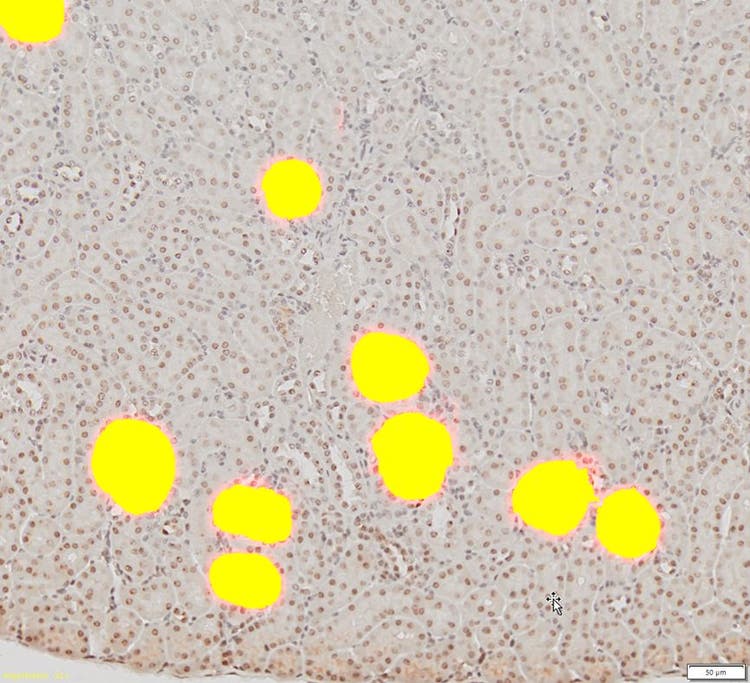

2. Les glomérules sont détectés et séparés par le réseau neuronal profond entraîné.

Glomérules détectés et séparés par le réseau neuronal profond entraîné

3. Les glomérules détectés peuvent être segmentés et utilisés en vue d’effectuer d’autres analyses de numération et de mesure sur l’image de sortie.

Glomérules détectés